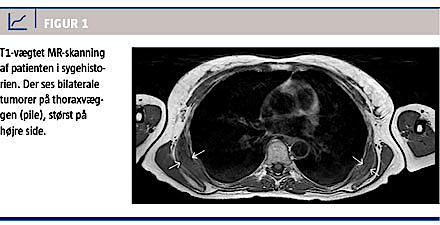

En 55-årig kvinde blev henvist til Ortopædkirurgisk Ambulatorium på Sydvestjysk Sygehus i april 2011 med en hævelse under højre scapulas nedre pol. Hun havde ikke tidligere været udsat for særlig grad af repetitiv skulderbelastning hverken ved arbejde eller fritidsaktivitet. Hun havde gennem flere år bemærket en bule samt springende klikfænomener som eneste symptomer, og kun på højre side. En MR-skanning

viste bilaterale tumorer under scapula. På højre side målte tumoren 55 × 55 × 15 mm, på venstre side

40 × 40 × 5 mm (Figur 1). Tumorvævet havde samme signalintensitet og antydning af samme la-